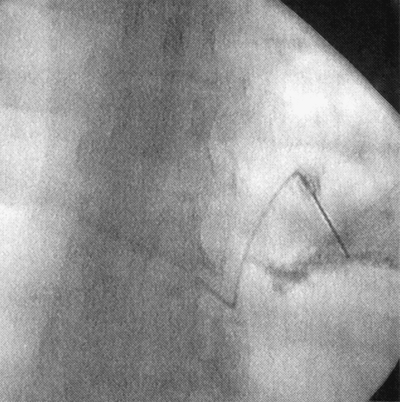

Figure 20-3. Procedure done under fluoroscopy. -

If the procedure is done under

fluoroscopy, injection of 1 mL of contrast will confirm placement of

the needle within the neurovascular space (Fig. 20-3).